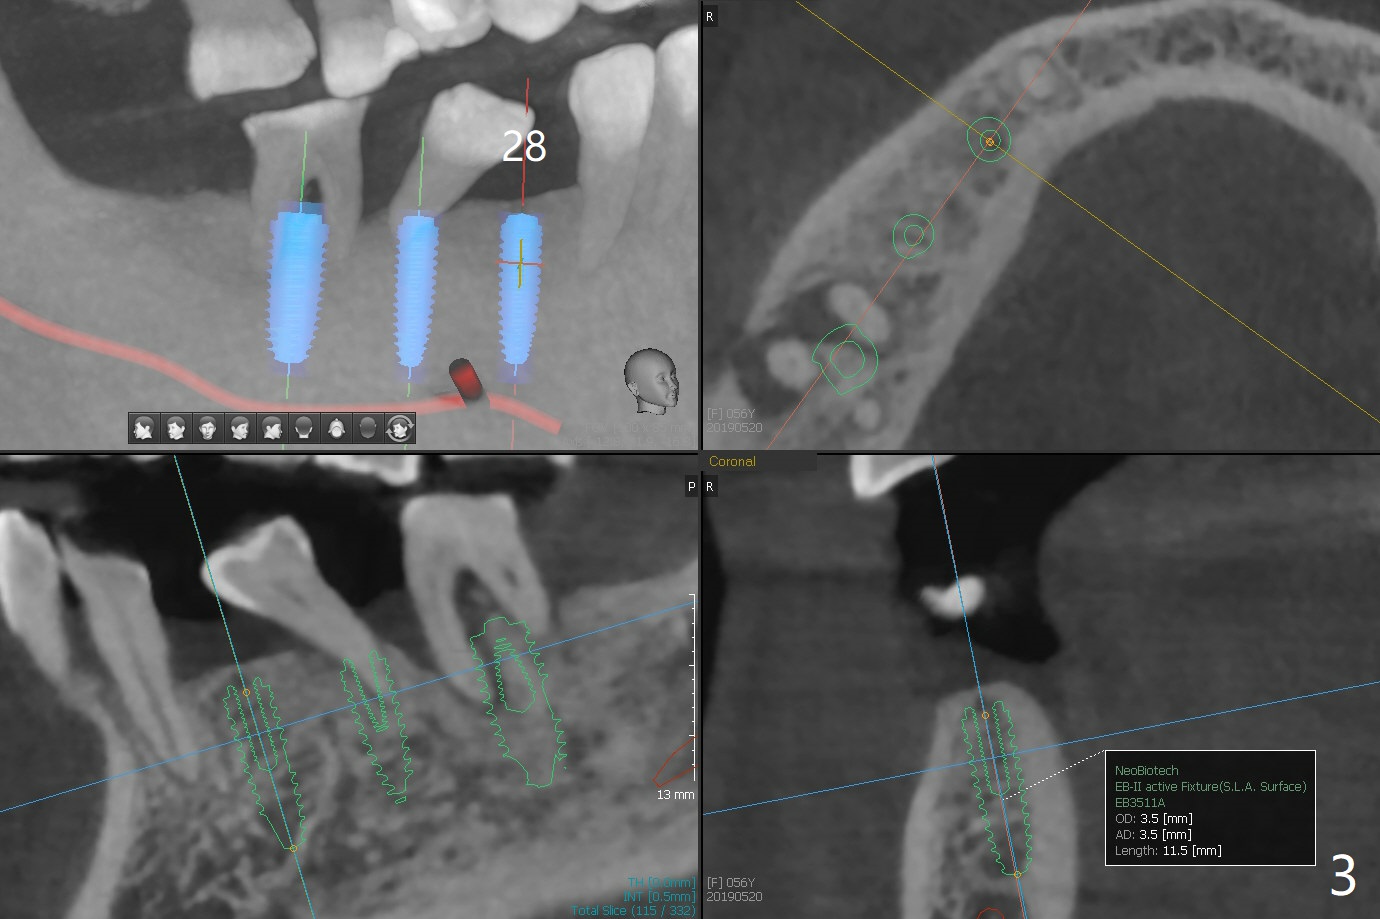

A 56-year-old woman does not want implant FPD at #18-20 six months post #18 and 20 implant placement. She agrees not to save the teeth #29 and 30 (Fig.1,2). An implant will be placed at #28 (Fig.3).